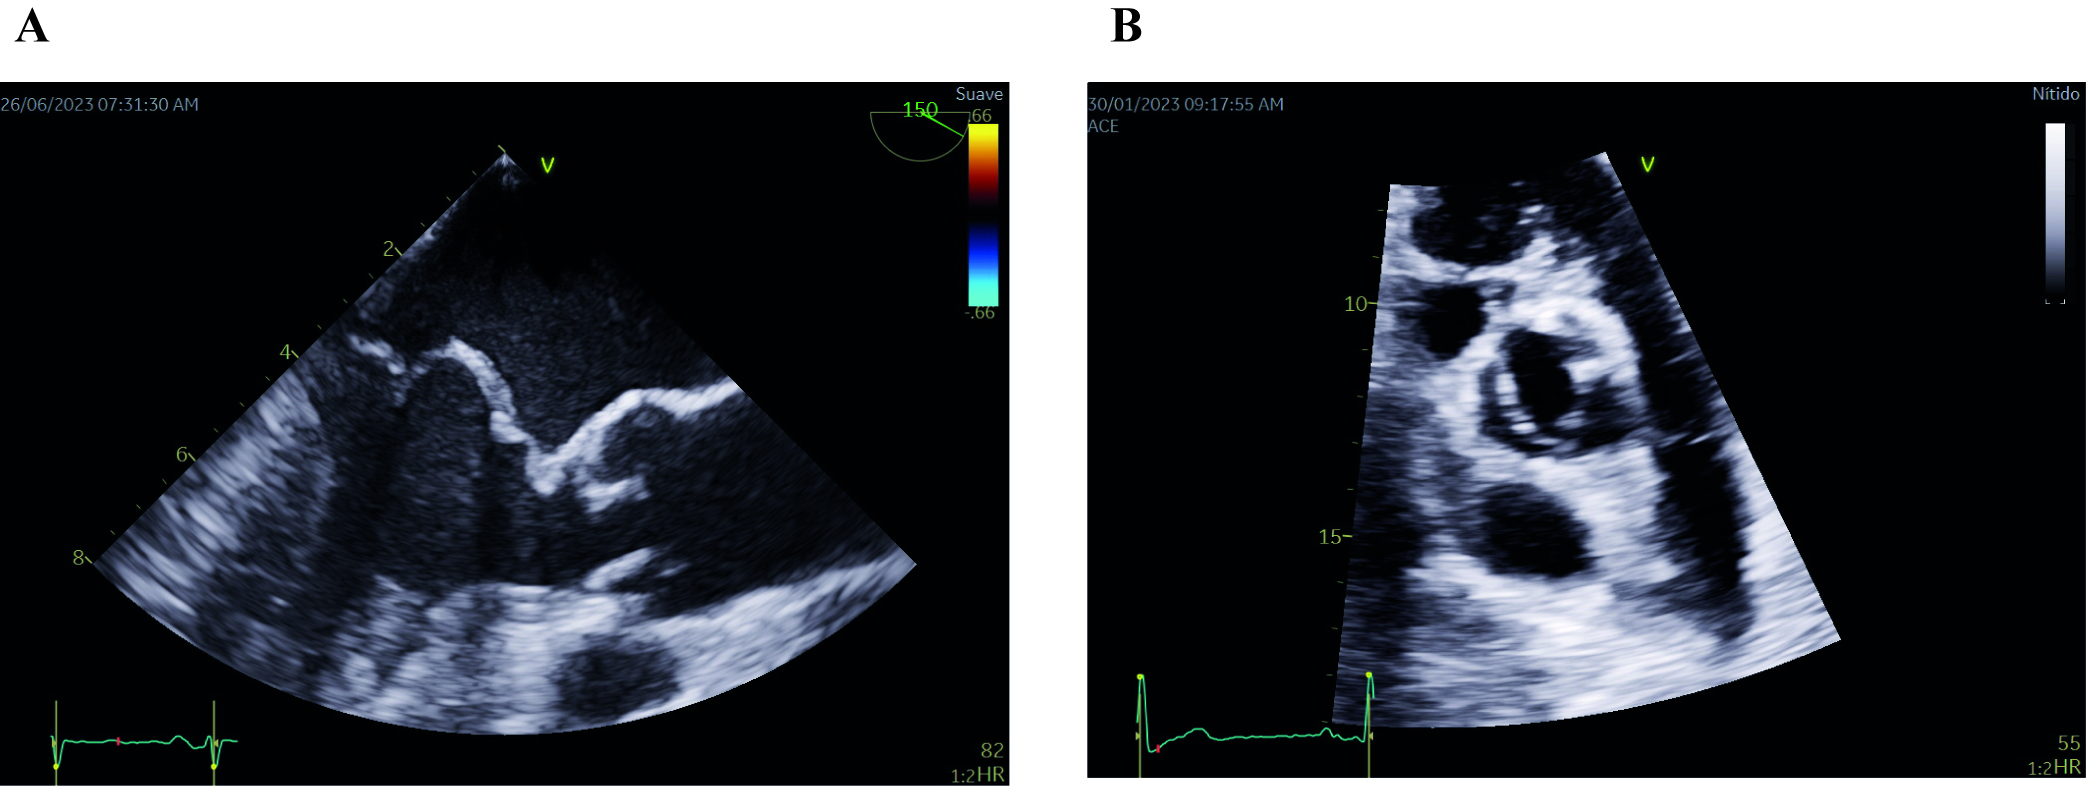

Fig. 2.

Fig. 2.Echocardiographic images of mitral valve prolapse of both leaflets (A) and bicuspid aortic valve (B). (A) Midesophageal long-axis transesophageal echocardiographic image depicting mitral valve prolapse of both leaflets. Note that both leaflets are beyond the valvular plane, protruding into the left atrium, when the mitral valve is closed (B) Parasternal short-axis transthoracic echocardiographic image showing a bicuspid aortic valve with fusion of both coronary leaflets. A raphe is present between the fused leaflets.

BAV is the prevailing valve abnormality found in around 0.5–2% of the general population [48]. It is characterized by an aortic valve that has only two cusps, or flaps, instead of the usual three (Fig. 2B). BAV follows an autosomal pattern of inheritance with incomplete penetrance, variable expressivity and male predominance in a 3:1 ratio [49]. More than 35% of individuals with BAV will experience various complications, including aortic valve stenosis and regurgitation, as well as ascending aortic aneurysms and dissection. Studies have shown a high incidence of thoracic aortic aneurysms (TAA) in BAV patients and their family members, suggesting that both TAA and BAV may share a common genetic cause [50, 51].